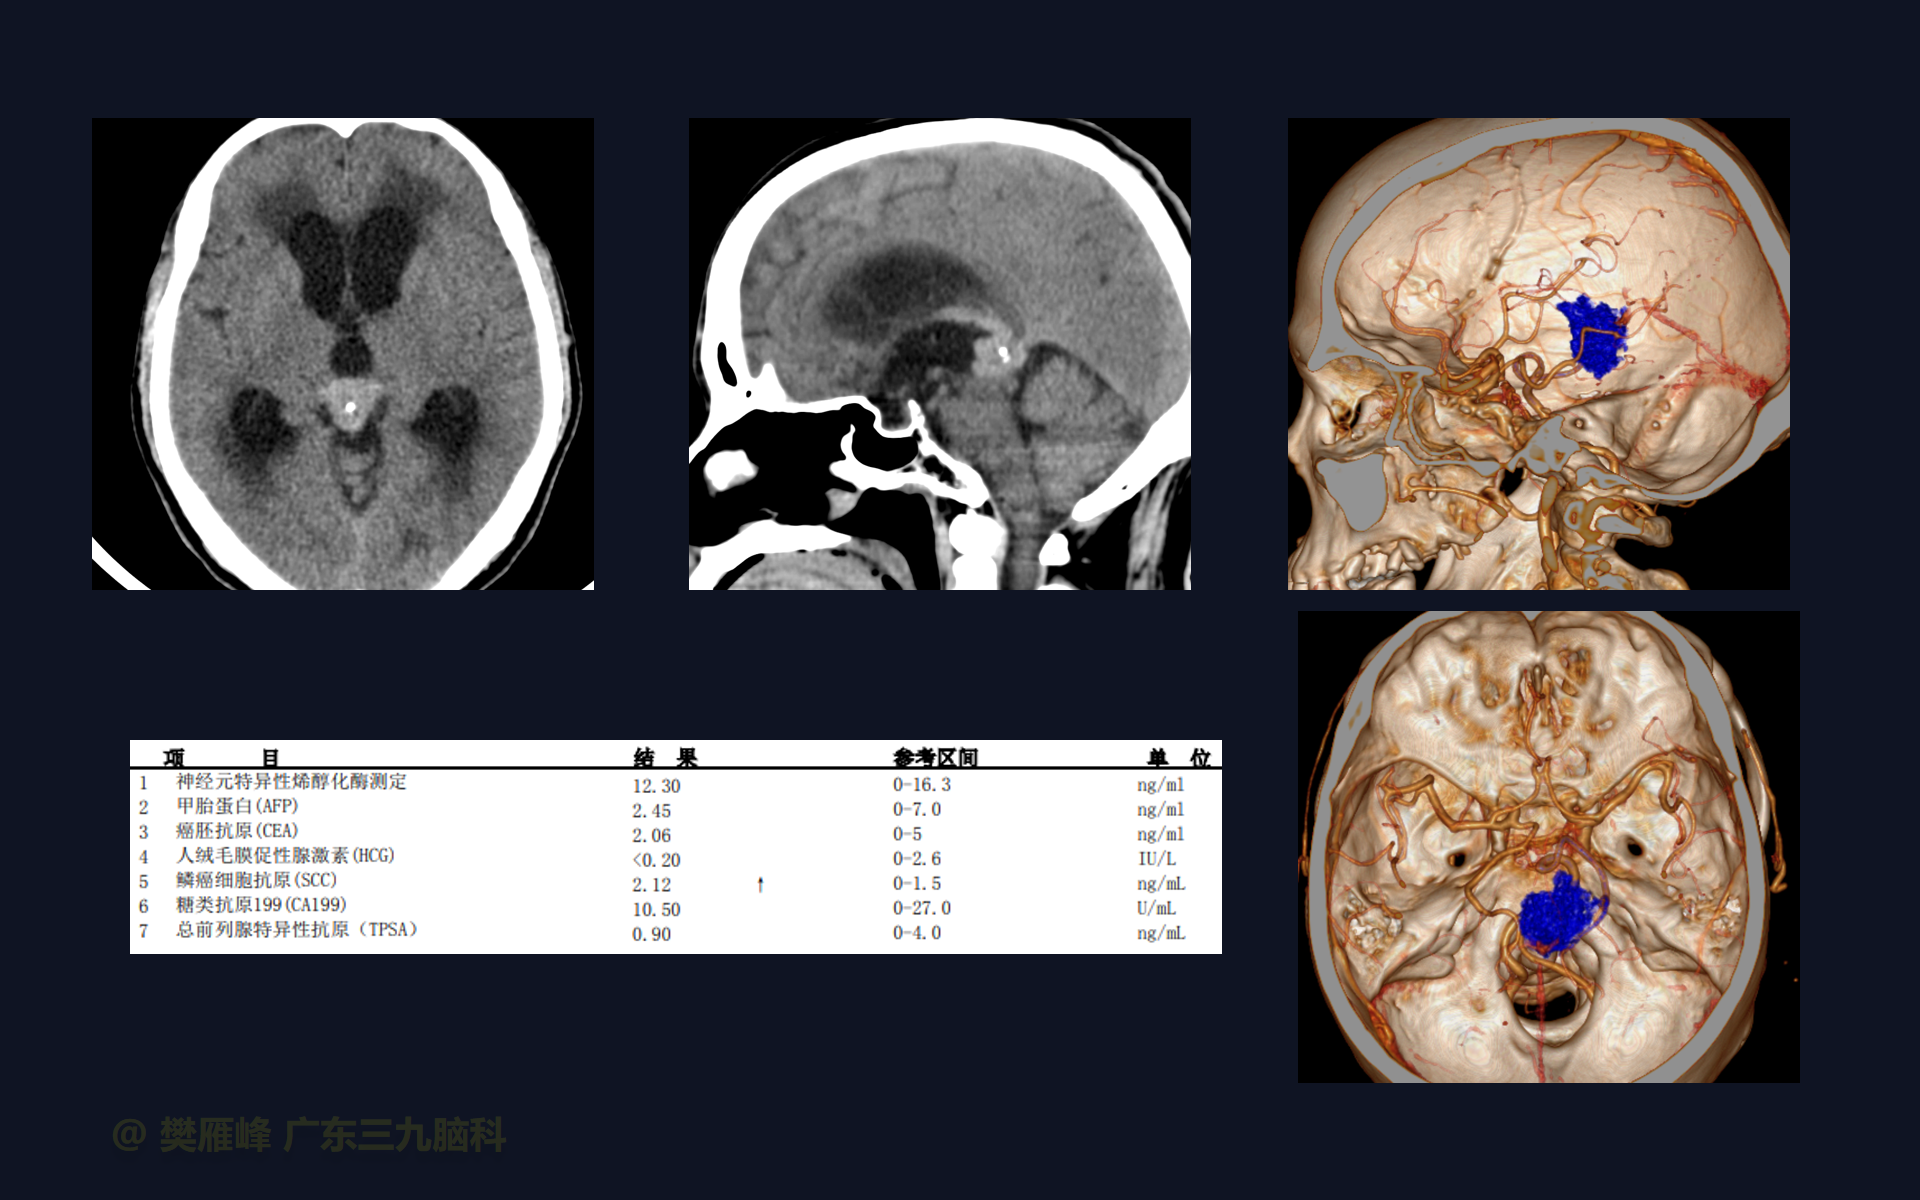

在这个二维手术视频中,展示了2例神经内镜下三脑室底造瘘+活检治疗三脑室后部肿瘤的方法。患者均为三脑室后部病变导致的梗阻性脑积水,病理结果1例为生殖细胞瘤,1例为淋巴瘤,在经过术后的放化疗病情均得到控制,生活质量满意。我们展示了安全的病变活检和第三脑室造瘘的技术要点,以最大限度减少术后继发脑积水和早期并发症。